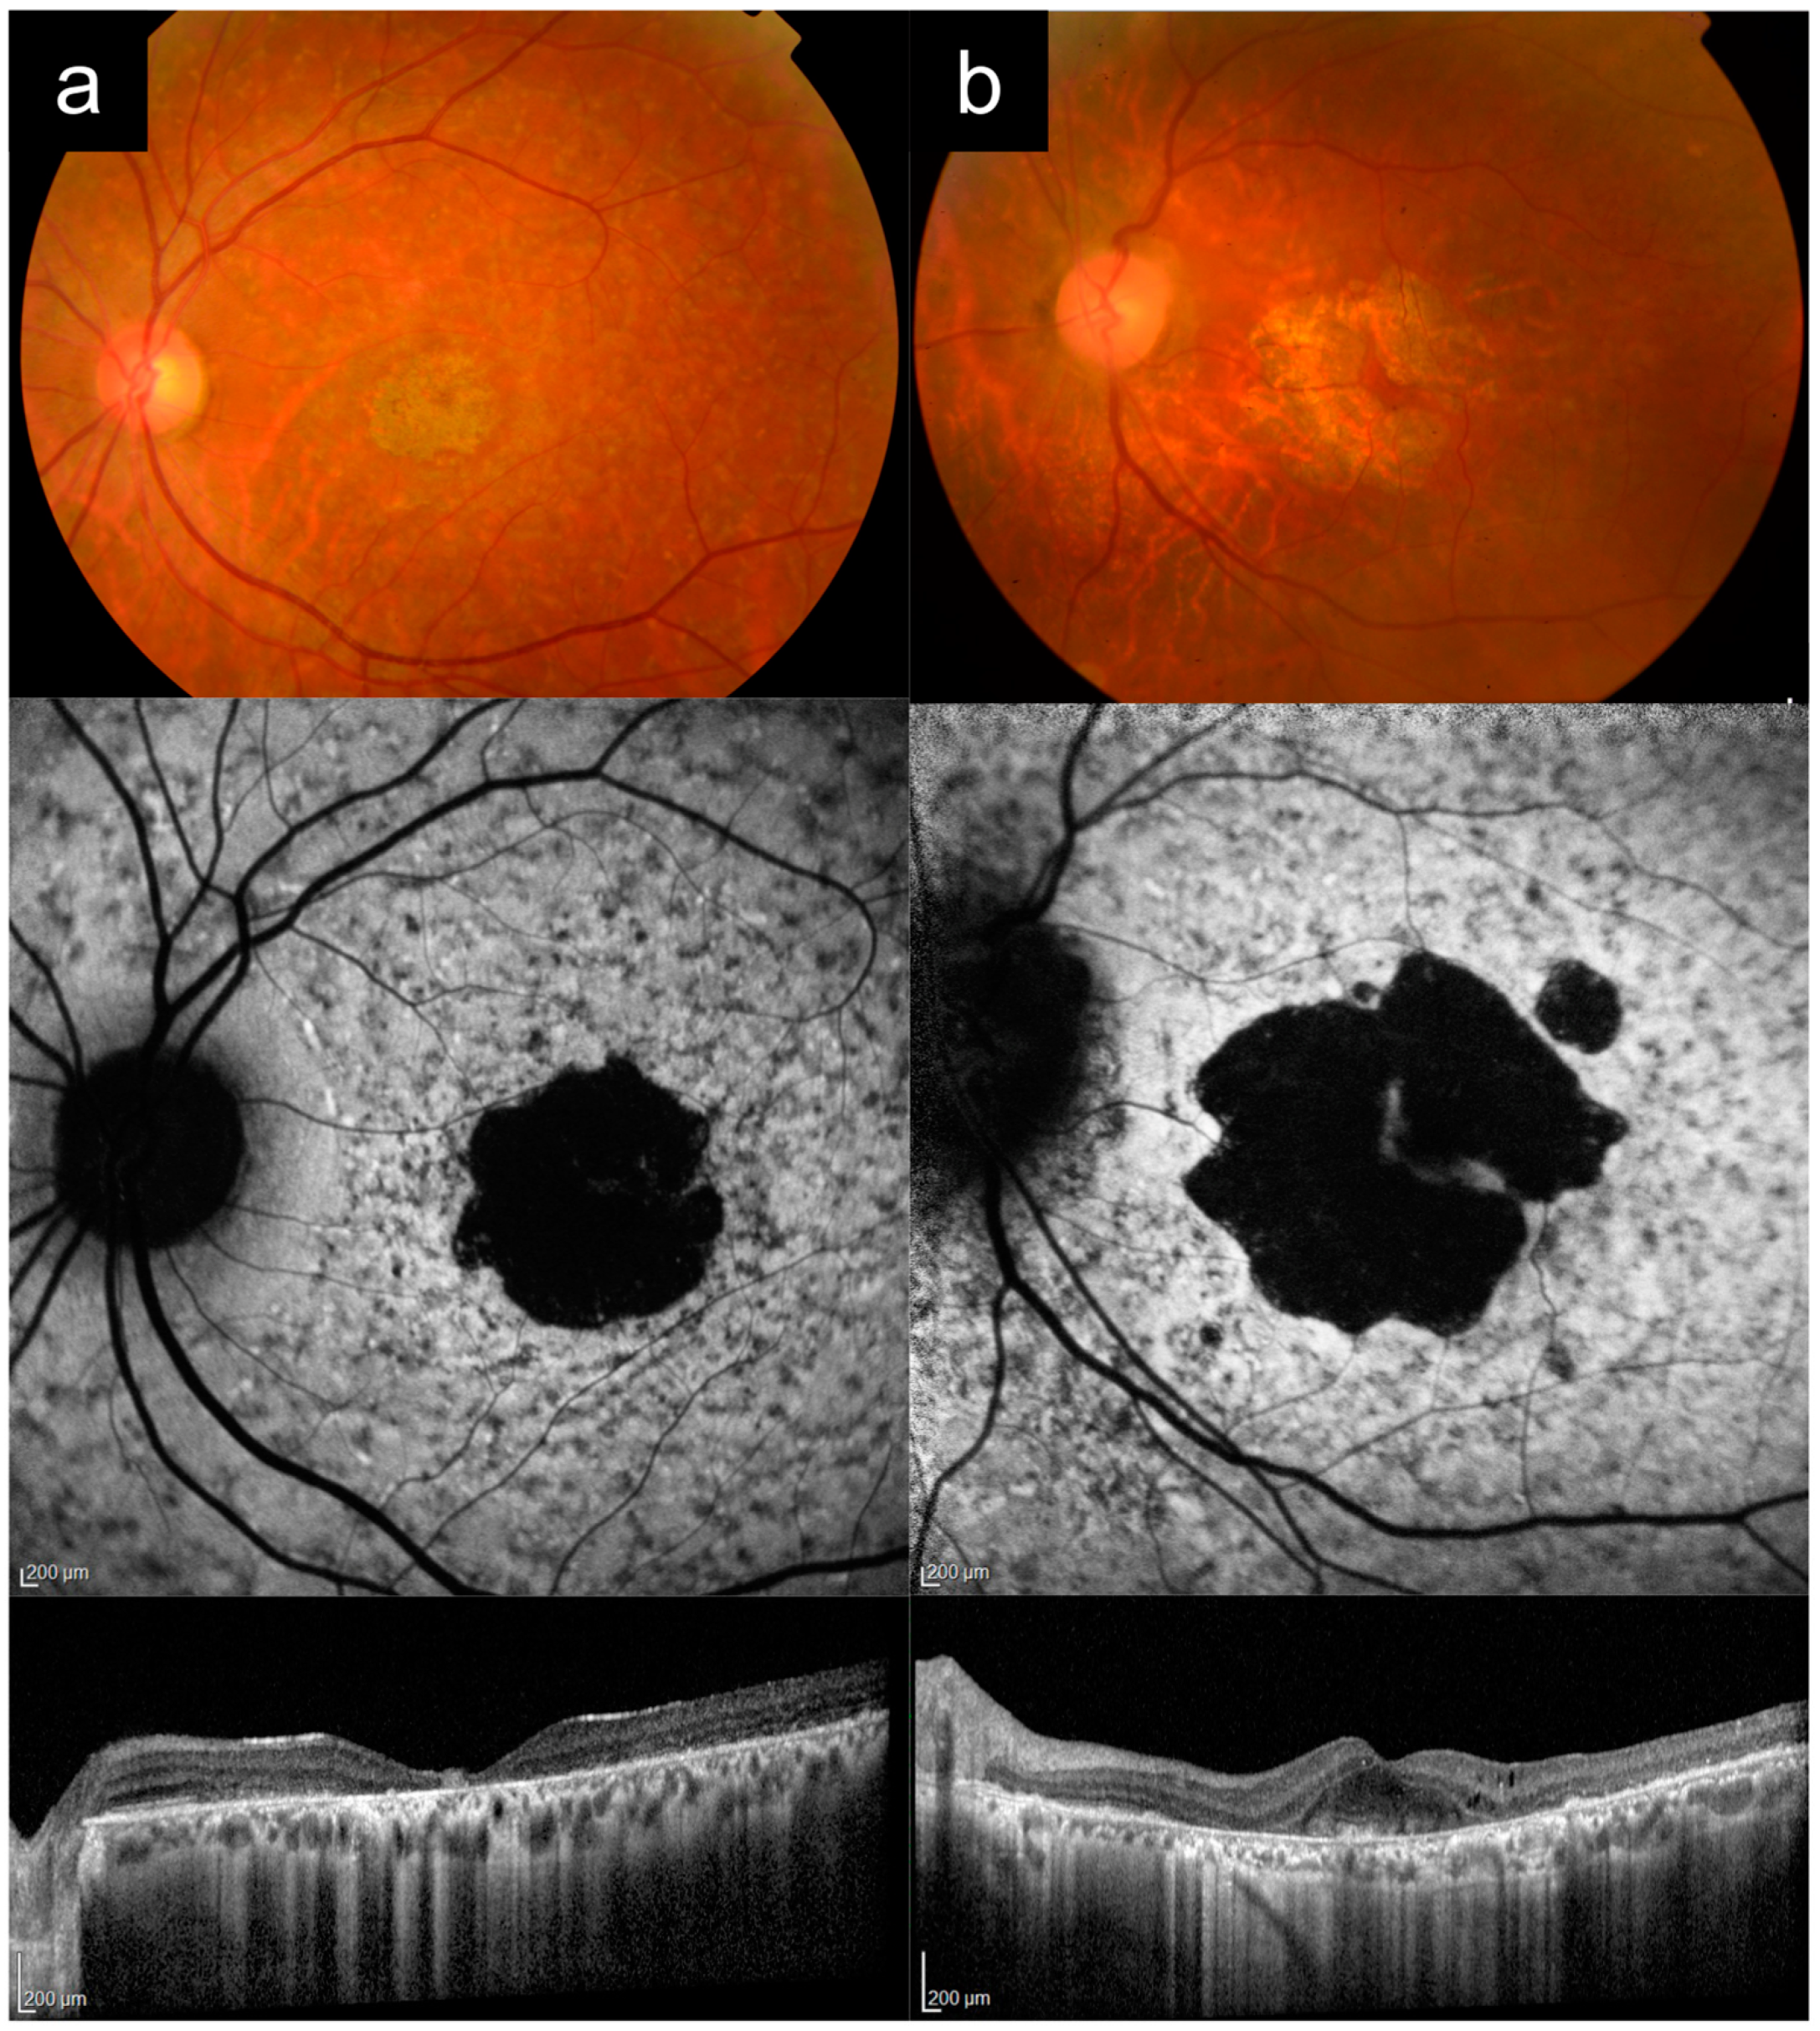

Case 1a presented with bilateral blurred central vision at 15 years of age, which progressively worsened over time. There were no other affected family members, consistent with autosomal recessive (AR) inheritance.

Figure 1a shows multimodal imaging from when the patient was in his 30s. VA in the left eye at that time was 6/45. Fundus examination and CFP imaging showed an area of foveal retinal pigment epithelium (RPE) atrophy with a granular appearance and metallic sheen, surrounded by yellow pisciform flecks distributed throughout the posterior pole and out to the mid-peripheral retina. AF imaging showed a central geographic patch of hypo-AF surrounded by flecks with mixed hyper- and hypo-AF signal. Note the typical sparing of the peripapillary retina, which is more obvious on AF imaging, but also visible on CFP, albeit more subtle. OCT imaging showed outer retinal atrophy and ellipsoid zone (EZ) loss, with patchy choroidal hypertransmission, again with notable peripapillary sparing. Genetic testing revealed two likely pathogenic

Case 1b presented with complaints of persistent blurred vision and mild metamorphopsia in the left eye after uneventful cataract surgery in his late 60s. Best-corrected VA (BCVA) by manifest refraction was 6/7.5.

Figure 1b shows imaging from this time, after his cataract surgery. CFP imaging showed a broad annulus of perifoveal RPE atrophy, with sparing of a small foveal island (explaining the good vision). In the rest of the macula, there were areas of subtle RPE atrophic change, but no frank flecks or yellow subretinal deposits. AF imaging, however, revealed much more apparent fleck-like lesions, although there was no peripapillary sparing. OCT imaging showed perifoveal RPE and outer retinal atrophy, with relative sparing of a small subfoveal region. Prior to genetic testing results, this patient had been diagnosed by multiple specialists as having “late onset Stargardt disease”. Genetic testing subsequently identified the

PRPH2 c.533A>G p.Q178R variant. Pedigree by history revealed that the subject’s mother was also likely affected, which was consistent with an autosomal-dominant (AD) pattern of inheritance.

Case 1a represents a typical phenotype of

ABCA4-RD, presenting with adolescent-onset “classical” Stargardt disease with macular atrophy, flecks, and peripapillary sparing [

16,

24,

25]. Case 1b is a

PRPH2-associated macular dystrophy mimicking Stargardt disease. Key distinguishing features between these two cases are the age of onset, peripapillary sparing, and the inheritance pattern from the pedigree (

Table 2). The younger age of onset in adolescence, presence of clear peripapillary sparing, and the AR inheritance pattern all favor a diagnosis of

ABCA4-RD versus

PRPH2-RD. Note that the yellow deposits or flecks and AF appearance can look very similar in both diseases, as in this case. In addition, the small area of central foveal sparing in Case 1b, though absent in this Case 1a, can also occur in

ABCA4-RD, as in Case 4a later.